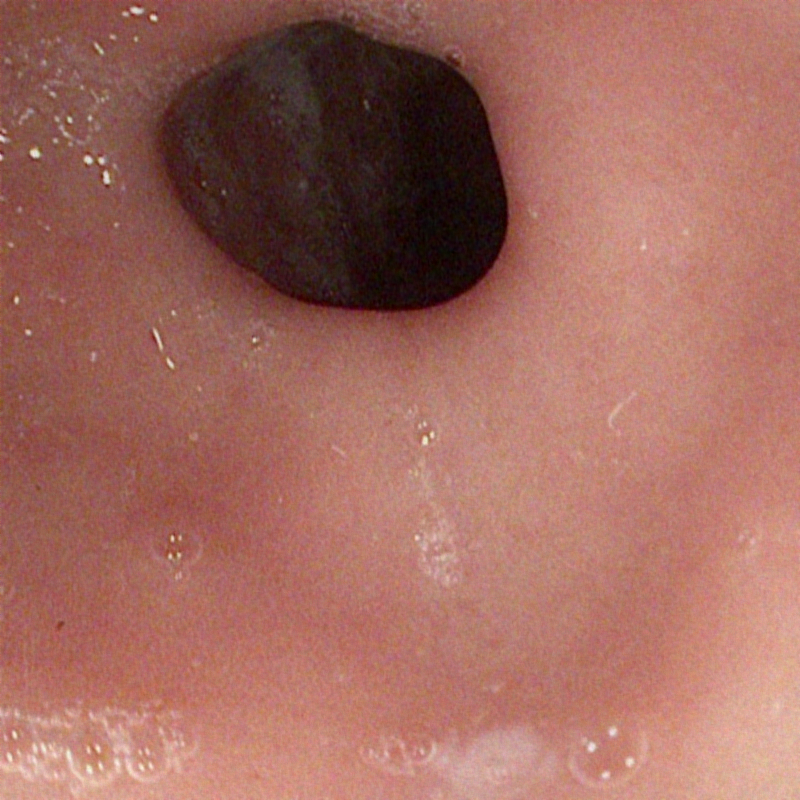

| (a) Input | (b) LIME | (c) HDRNet | (d) LECCM | (e) SwinIR | (f) NAFNet | (g) EndolMLE | (h) Ours | (i) GT |

The proposed method was evaluated on a synthetic dataset. All deep learning-based methods were fine-tuned based on E-kvasri. Figure 2 presents sample results of the proposed method and comparative methods on four endoscopic images from the E-kvasri.